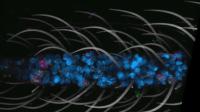

Экспериментальная гибридная терапия вылечила диабет 1 типа у мышей

Экспериментальная гибридная терапия продемонстрировала высокий потенциал в лечении диабета 1 типа у мышей. Специально разработанный метод лечения показал стопроцентную эффективность в предотвращении развития болезни у животных в преддиабетическом состоянии и смог обратить вспять состояние у мышей с полностью развившимся заболеванием. Уникальность нового подхода заключается в успешном объединении клеток иммунной системы мыши-реципиента и мыши-донора, что позволило им сосуществовать в гармонии без необходимости применения иммунодепрессантов на протяжении как минимум четырёх месяцев.